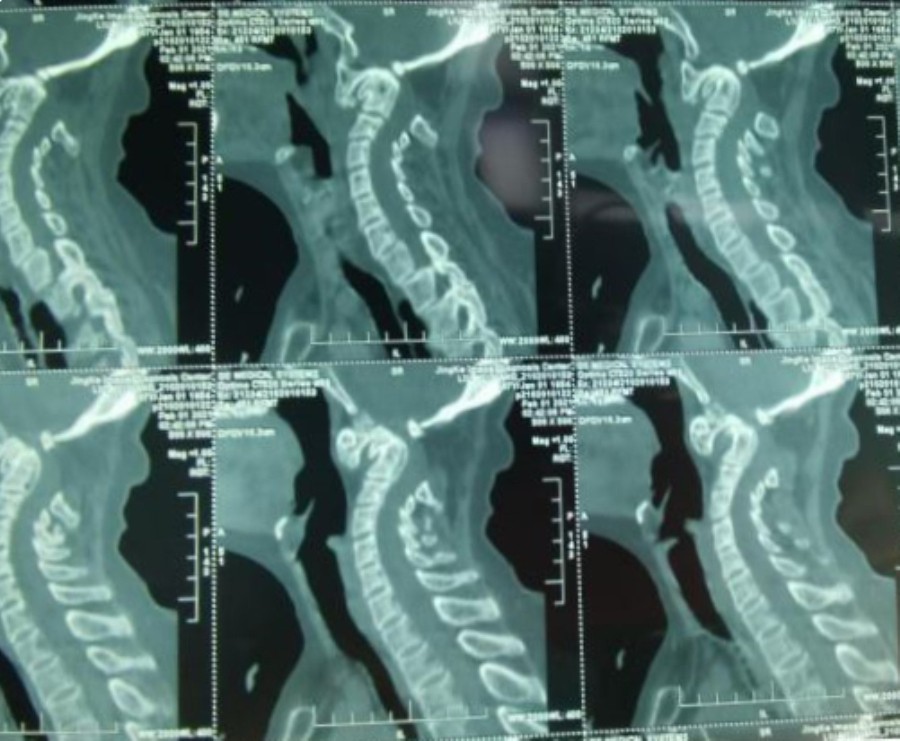

患者67岁,4个月前无明显诱因出现四肢麻木僵硬无力,不能自行站立、行走,曾行针灸治疗效果不明显,且症状逐渐加重。在进一步寻求诊疗的过程中,于今年年初慕名来我院找到颈椎外科张沛主任就诊。张主任结合颅脑和颈椎的相关检查,经阅片查体后诊断为“1、寰枢椎脱位;2、先天性齿状突发育不良;3、慢性脊髓病”而收入住院治疗。

术前颈椎CT